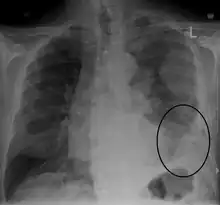

![]() | |

| CT scan showing a left sided mesothelioma with an enlarged mediastinal lymph node | |

More than 80% of mesothelioma cases are caused by exposure to asbestos.[3] The greater the exposure the greater the risk.[3] As of 2013, about 125 million people worldwide have been exposed to asbestos at work.[13] High rates of disease occur in people who mine asbestos, produce products from asbestos, work with asbestos products, live with asbestos workers, or work in buildings containing asbestos.[3] Asbestos exposure and the onset of cancer are generally separated by about 40 years.[3] Washing the clothing of someone who worked with asbestos also increases the risk.[13] Other risk factors include genetics and infection with the simian virus 40.[3] The diagnosis may be suspected based on chest X-ray and CT scan findings, and is confirmed by either examining fluid produced by the cancer or by a tissue biopsy of the cancer.[2]

Diagnosing mesothelioma is often difficult because the symptoms are similar to those of a number of other conditions. Diagnosis begins with a review of the patient's medical history. A history of exposure to asbestos may increase clinical suspicion for mesothelioma. A physical examination is performed, followed by chest X-ray and often lung function tests. The X-ray may reveal pleural thickening commonly seen after asbestos exposure and increases suspicion of mesothelioma.[15] A CT (or CAT) scan or an MRI is usually performed. If a large amount of fluid is present, abnormal cells may be detected by cytopathology if this fluid is aspirated with a syringe.[11] For pleural fluid, this is done by thoracentesis or tube thoracostomy (chest tube); for ascites, with paracentesis or ascitic drain; and for pericardial effusion with pericardiocentesis. While absence of malignant cells on cytology does not completely exclude mesothelioma, it makes it much more unlikely, especially if an alternative diagnosis can be made (e.g., tuberculosis, heart failure). However, with primary pericardial mesothelioma, pericardial fluid may not contain malignant cells and a tissue biopsy is more useful in diagnosis.[11] Using conventional cytology diagnosis of malignant mesothelioma is difficult, but immunohistochemistry has greatly enhanced the accuracy of cytology.